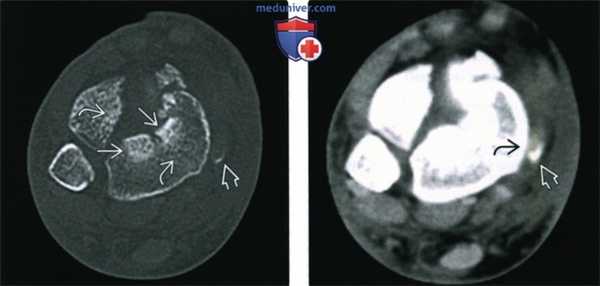

(Слева) При КТ в аксиальной плоскости определяются линии переломов, разделяющие нижнюю суставную поверхность большеберцовой кости на множество мелких и три крупных фрагмента - переднелатеральный, задний и медиальный. Склероз обусловлен сдавливанием костных фрагментов/трабекул. Небольшой костный фрагмент с медиальной стороны образовался вследствие отрывного перелома места прикрепления удерживателя сухожилий сгибателей.

(Справа) У этою же пациента при КТ в аксиальной плоскости в мягкотканном режиме отмечается смещение сухожилия задней большеберцовой мышцы кпереди. Позади него выявляется костный фрагмент, отделившийся вследствие отрывною перелома области прикрепления удерживателя сухожилий сгибателей.